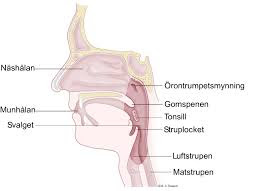

Andningsorganen

Andningsorganen är näshålan, luftstrupen, luftrören, lungorna.